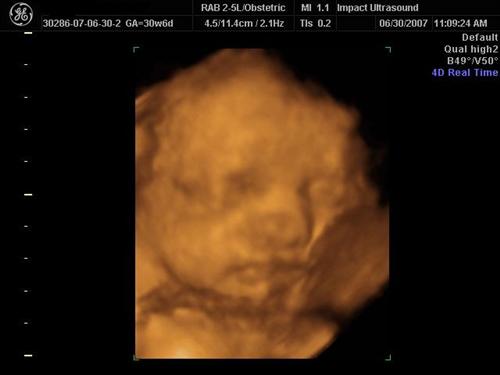

We went to Impact Medical Technologies today for our 3D/4D sono! It was alot of fun! Our normally sleepy, non-cooperative baby was awake and soooo active the entire time! They got some really great shots of her! Here are a few!

I think she looks alot like me in this one: